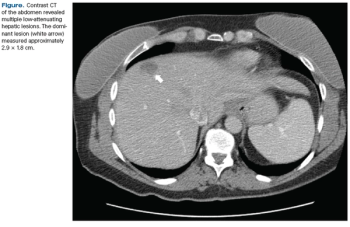

An asymptomatic 45-year-old woman presented for a screening mammogram and was noted to have a soft-tissue opacity with calcifications in the left breast. Ultrasound revealed a highly suspicious mass.